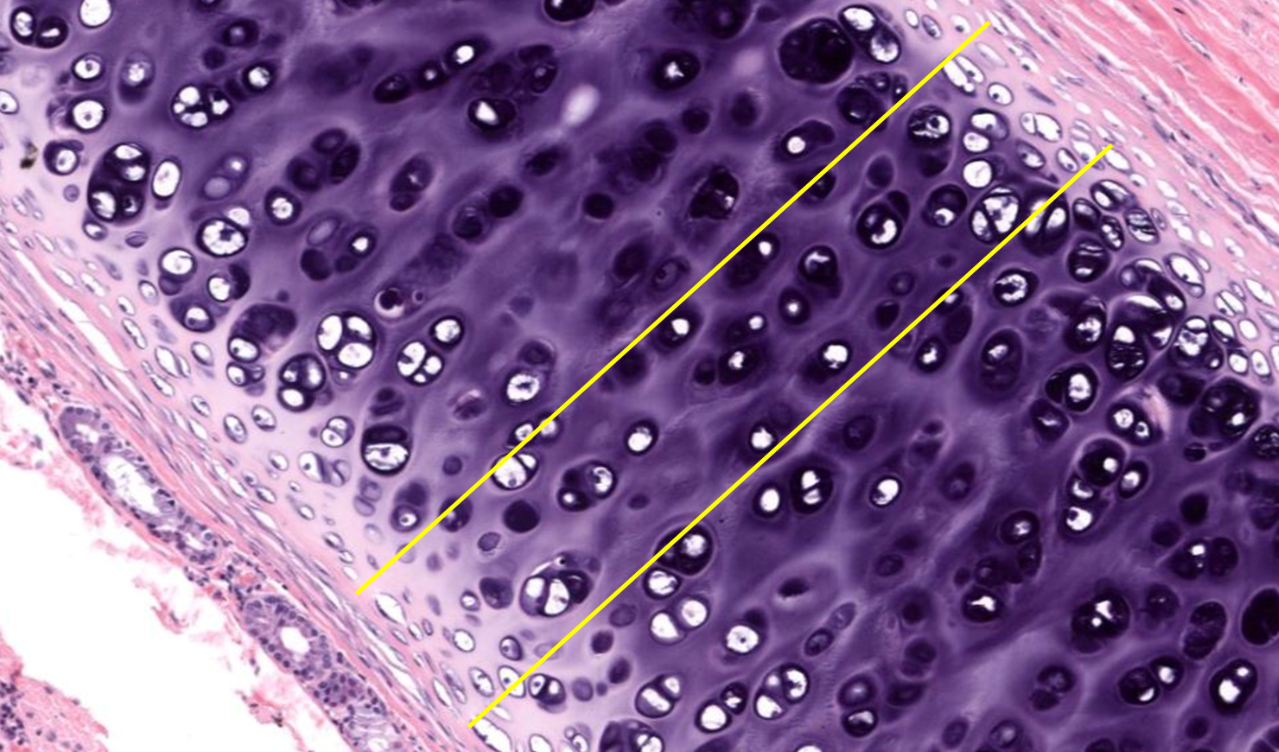

Cartilagem fibrosa